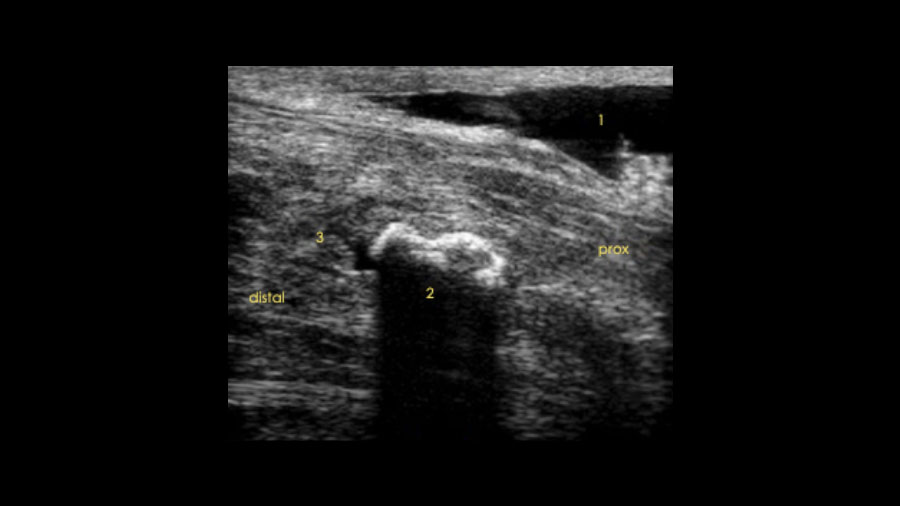

Ultrasound can be useful to document the position of the spike and its location relevant to the DDFT, with more medial and lateral bony protuberances causing no impingement on tendons as they pass over the caudal radius.

A recent case involved a 3‑year‑old Thoroughbred gelding with acute lameness and carpal sheath swelling, having successfully completed multiple races. Radiographs identified a large osteochondroma, and ultrasound confirmed marked disruption to the DDFT. Standard tenoscopic surgery was completed as above, identifying the osteochondroma extending deep into the DDFT. Removal was confirmed using radiography intra-operatively after debridement of the tendon lesion.